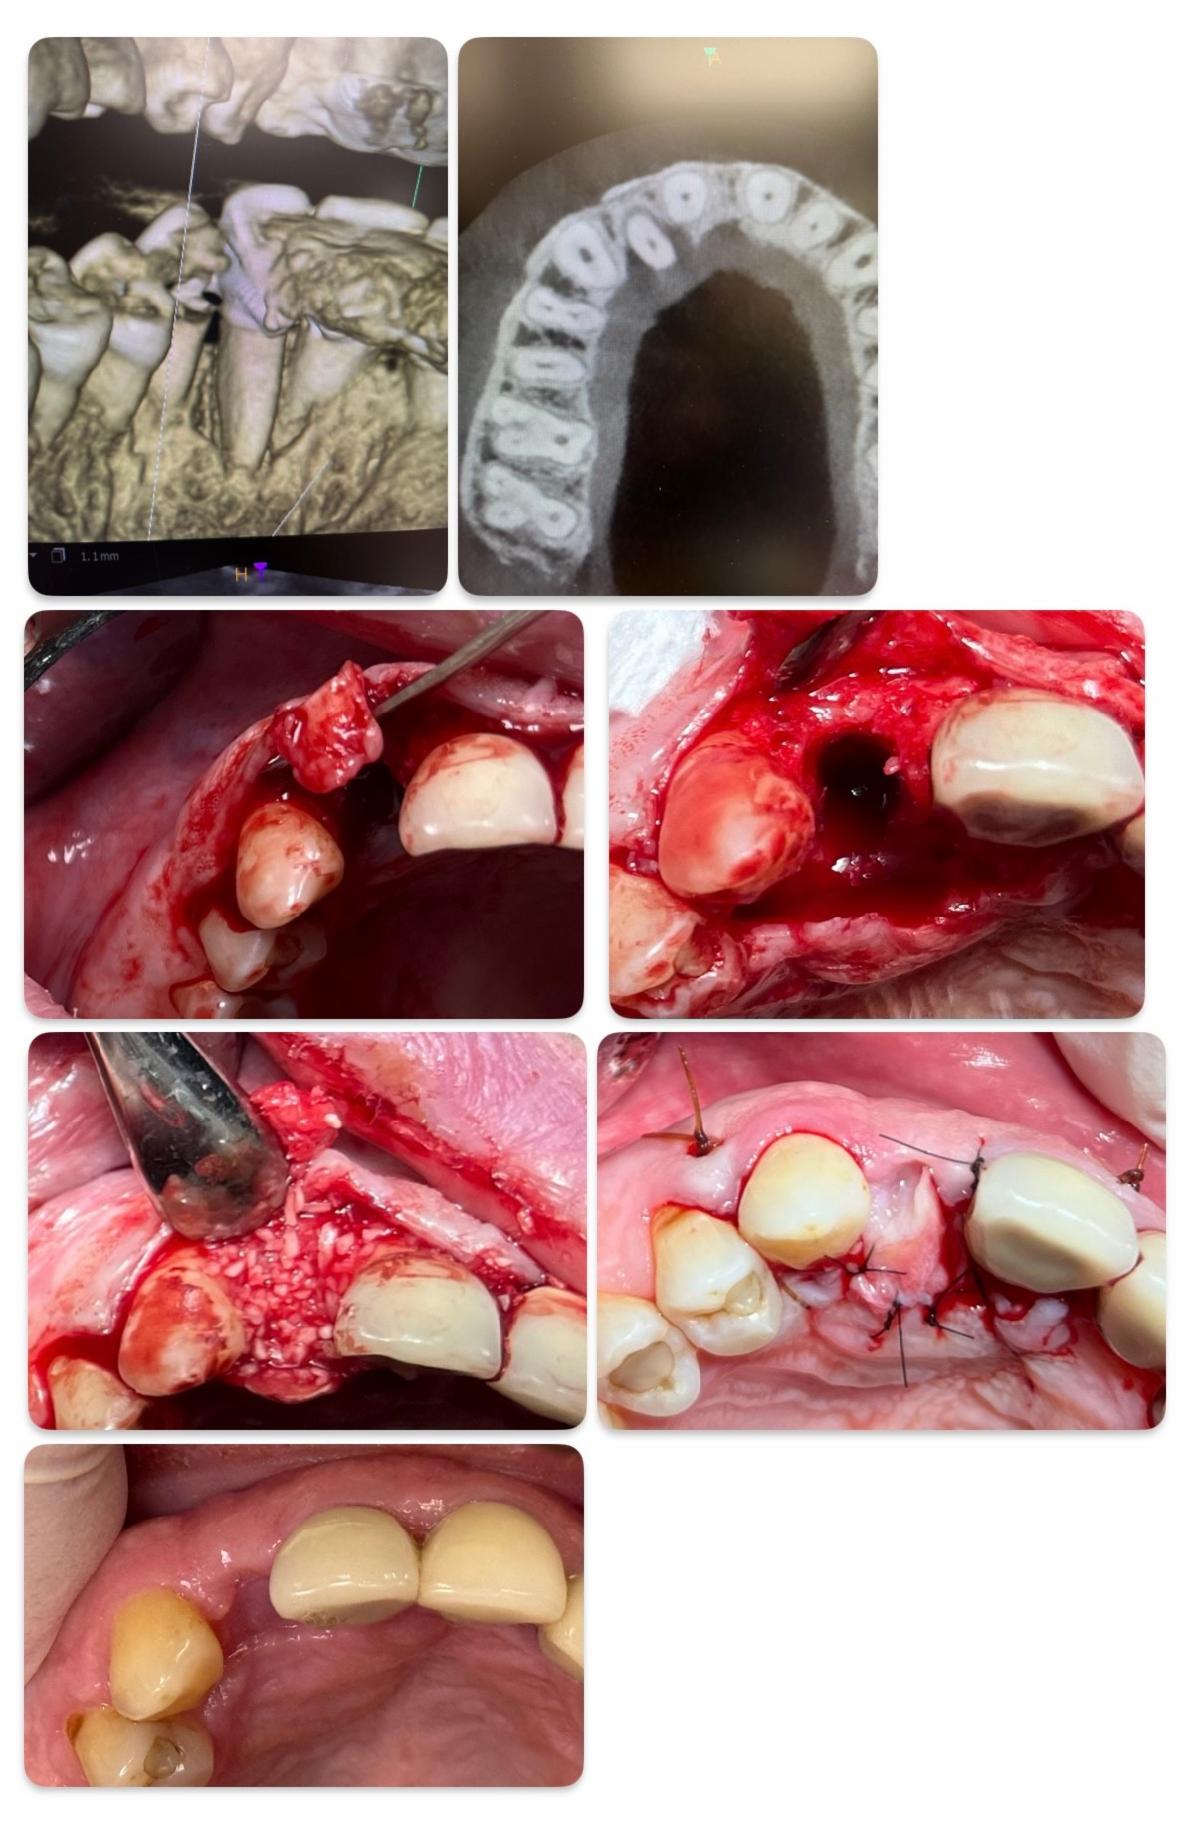

Case 2: Delayed Grafting Advantage

In this case, the extraction of tooth #7 was complicated by a palatal soft tissue dehiscence, making

tension-free primary closure a challenge. The socket was allowed to heal undisturbed for six weeks, during

which new connective tissue developed.

At the time of delayed grafting:

- The new tissue was dissected and used as a pedicle flap for tension-free closure

- No coronal flap advancement was needed

- The vestibular depth and mucogingival junction remained intact

This biologically guided approach preserved the native soft tissue anatomy and led to a superior esthetic result.